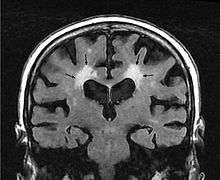

Leukoaraiosis[1] or white matter hyperintensities (WMHs)[2] are the nonspecific hyperintense changes in the cerebral white matter frequently seen on CT and MRI in aged individuals and even young adults sometimes.[3] It is a condition routinely found in elderly people.

The term leukoaraiosis was coined in 1986[4][5] by Hachinski, Potter, and Merskey as a descriptive term for rarefaction ("araiosis") of the white matter, showing up as decreased density on CT and increased signal intensity on T2/FLAIR sequences (white matter hyperintensities) performed as part of MRI brain scans.

These white matter changes are also commonly referred to as periventricular white matter disease, or white matter hyperintensities (WMH) due to their bright white appearance on T2 MRI scans. Many patients can have leukoaraiosis without any associated clinical abnormality. However, underlying vascular mechanisms are suspected to be the cause of the imaging findings. Hypertension, smoking, diabetes,[6] hyperhomocysteinemia, and heart disease are all risk factors for leukoaraiosis.